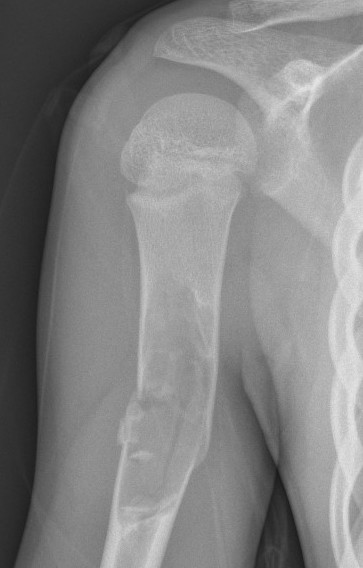

X-ray

Well-defined lucency

- thin sclerotic rim

- usually central

- thinned cortex with slight expansion

- thin internal septa

- can be multi-loculated

Fallen-Leaf (AKA fallen-fragment)

- with pathological fracture

- indicates that the lesion has no matrix and is fluid filled

Fallen leaf sign

Fracture

1. Humerus

Typically treat nonoperatively

Obtain union

Consider further intervention when fracture heals and UBC persists